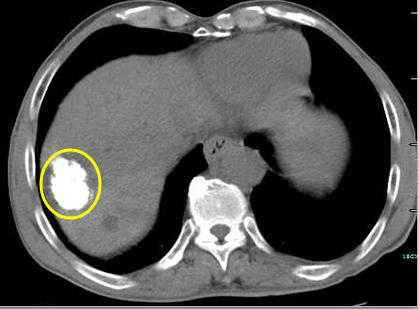

手术中,大爷的肿瘤病灶内外的血管都已经被栓塞剂堵上(黄圈内白色部分)